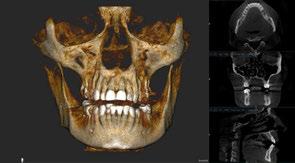

Fueron recolectados de forma retrospectiva datos sobre casos de implantes de 4,5 mm de longitud en los que fue realizada una carga inmediata. Todos los implantes fueron colocados en una única clínica en Vitoria, España, durante los años 2020 y 2021. Todos los pacientes fueron estudiados antes de la inserción de los implantes mediante modelos diagnósticos, exploración intraoral y realización de un TAC dental (Cone-beam) analizado posteriormente mediante un software específico (BTI-Scan III). Además, para planificar de forma correcta la posterior rehabilitación, se llevó a cabo un encerado diagnóstico,

Figuras 9 y 10. El primer paso para iniciar la rehabilitación se realiza mediante un escaneado intraoral para poder generar unos modelos tridimensionales exactos de la paciente elaborados mediante flujo digital y sobre ellos crear un encerado que nos dé la oclusión buscada y la posición ideal de los dientes a reponer.

Figuras 13-15. Imágenes del cone-beam de planificación de los cortes mandibulares de los tres implantes de 4,5 mm de longitud. Como podemos observar en los tres casos, la atrofia en altura es muy llamativa, habiéndose necesitado procedimientos regenerativos previos en caso de haber colocado implantes de longitud convencional.

Figura 16. Radiografía de la colocación de los implantes y la prótesis de carga inmediata horas después de la cirugía.

Figura 17. Radiografía final del caso con las prótesis definitivas, tras dos años de seguimiento, sin pérdidas óseas evidentes en ninguno de los implantes estudiados.